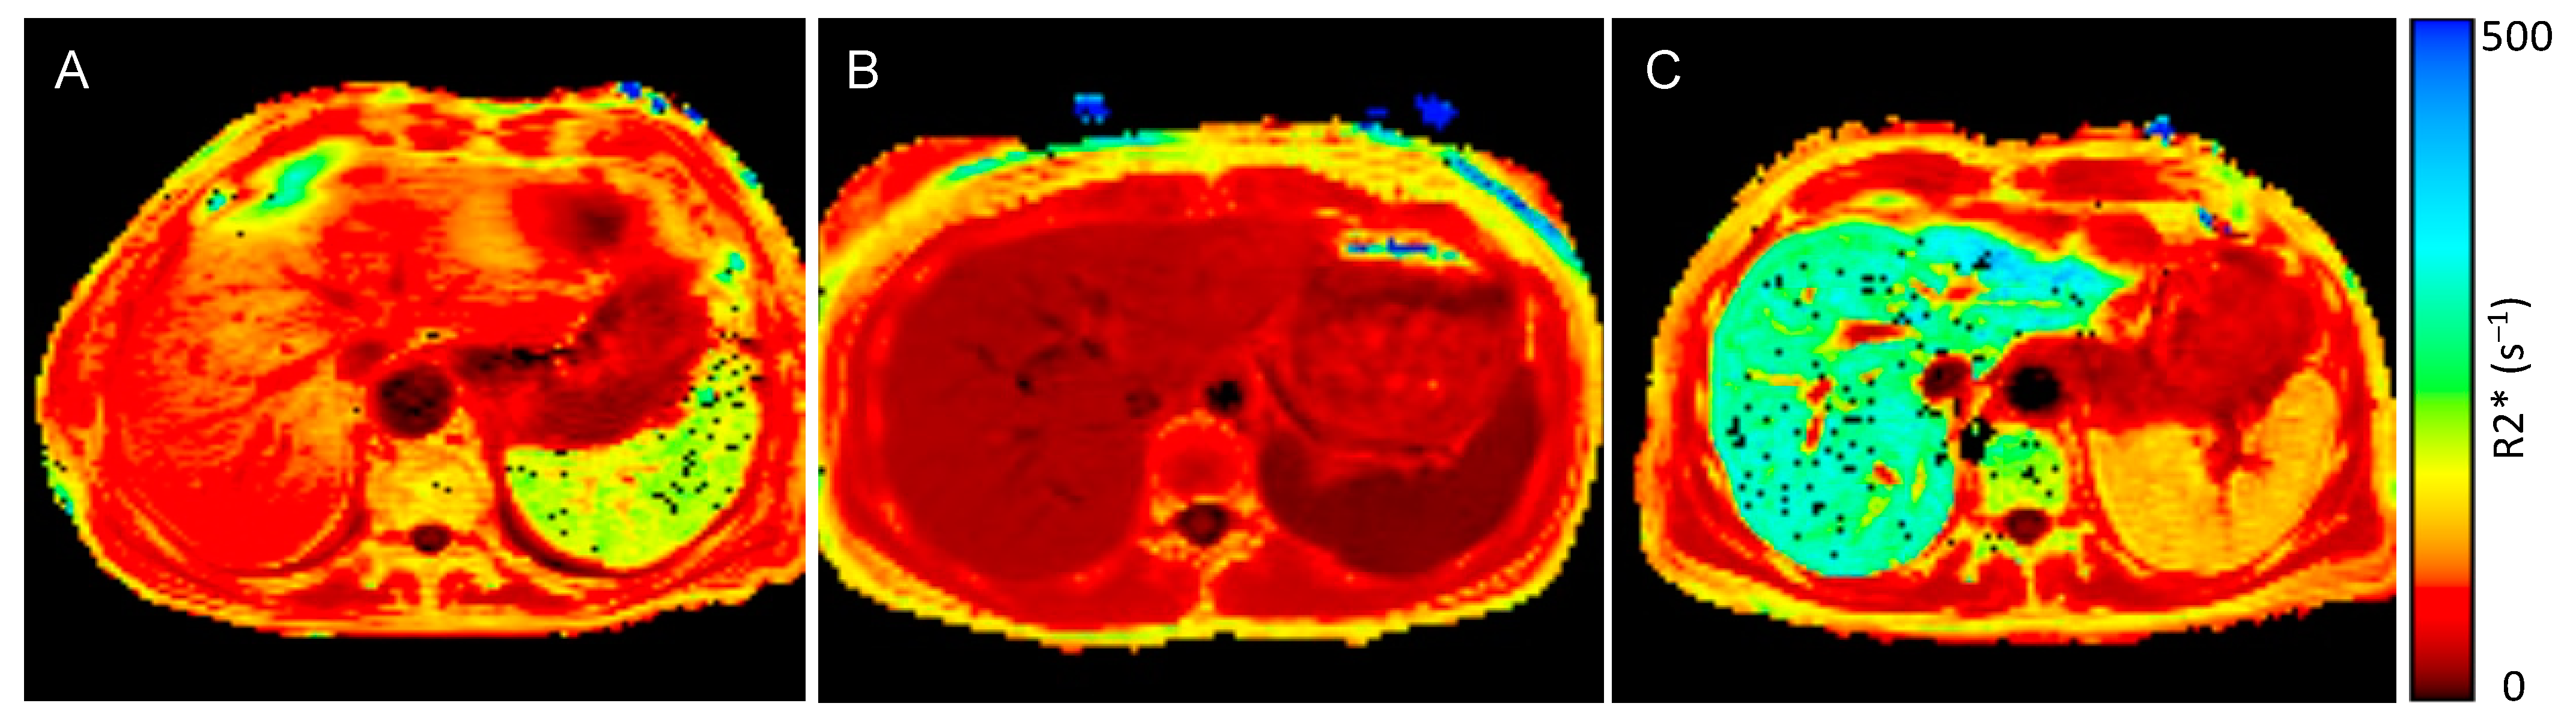

Patients with ESKD and anemia had significantly higher spleen (119.8 s−1 vs. 19.3 s−1, p < 0.001) and liver R2* values (90.1 s−1 vs. 36.1 s−1, p < 0.001) compared to healthy controls, while pancreas (31.0 s−1 vs. 24.9 s−1, p = 0.149) and heart R2* values (27.4 s−1 vs. 28.6 s−1, p = 0.583) did not significantly differ between the groups (Figure 1 and Figure 2). When applying the reference values used at our clinic [35], 85% of the ESKD patients (n = 17) had elevated spleen and 60% (n = 12) elevated liver R2* values, while their pancreas and heart iron R2* values were within the normal range.

Figure 1.

R2* values of spleen, liver, pancreas, and heart in patients with anemia in end-stage kidney disease (ESKD) and a control group of individuals without signs of inflammation. ESKD patients with anemia had significantly higher spleen and liver R2* values compared to otherwise healthy controls, while their pancreas and heart R2* values did not significantly differ.